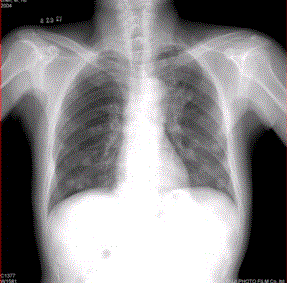

问题 患者男,45岁,因肝硬化、肝癌行肝移植术后6个月,咳嗽2周,来院复查。CR及CT影像如下图。 该疾病的转移途径可以为

选项 A.经肺动脉 B.经肺动脉至淋巴管而后到肺外围 C.经纵隔淋巴结逆流到肺门淋巴结,再经肺内淋巴管到肺外周 D.经胸膜腔 E.经气道 F.经支气管动脉

答案 ACDE